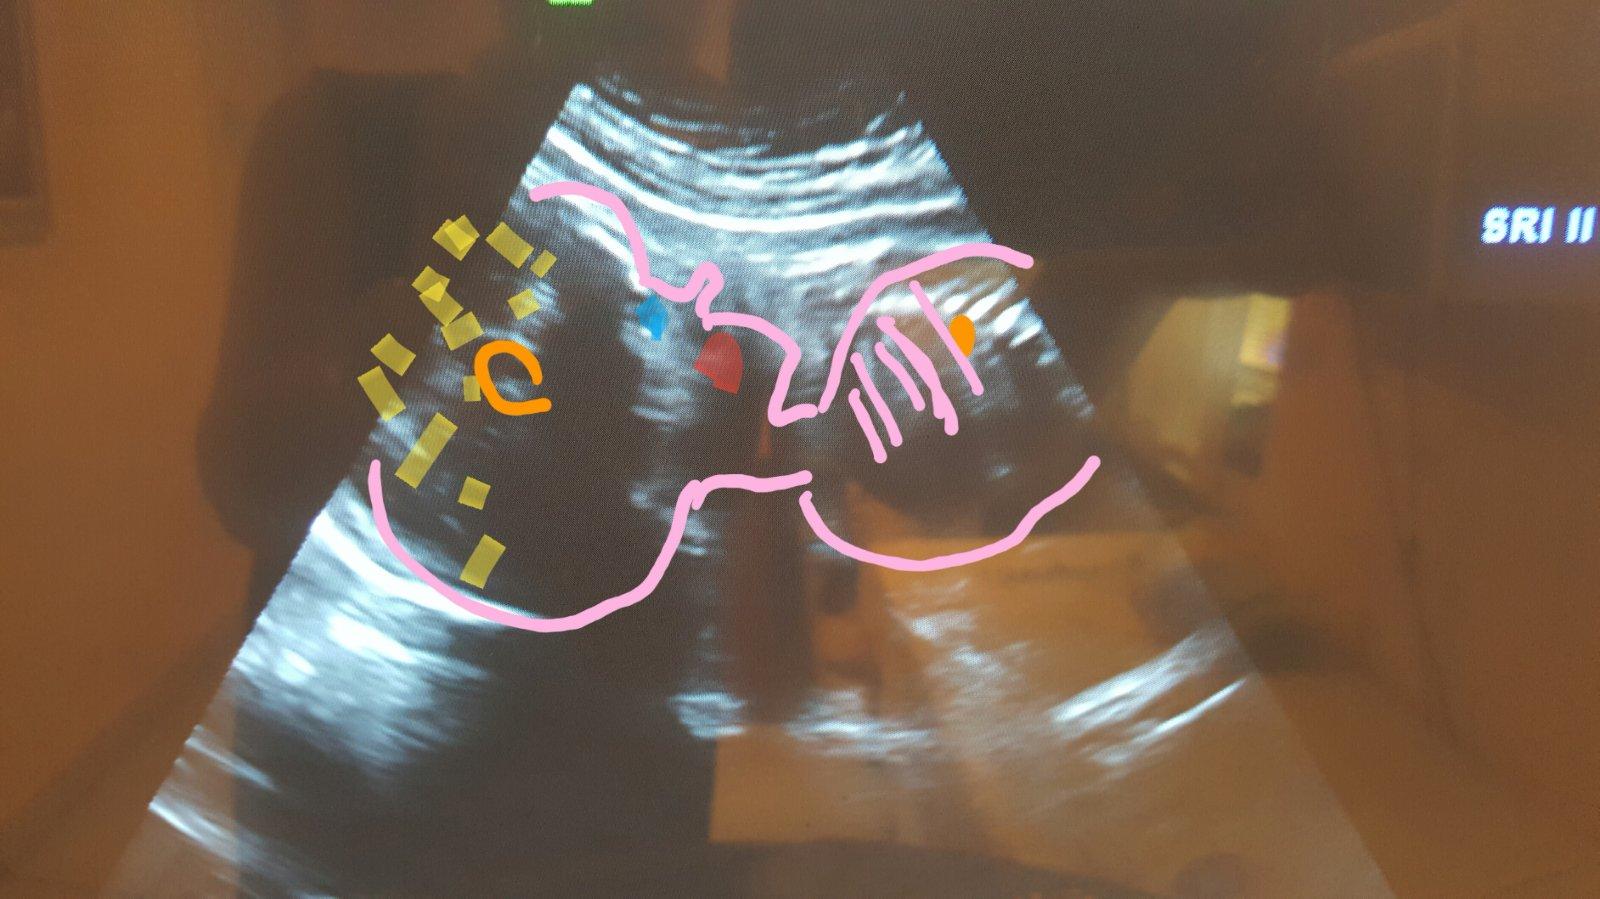

Moja najmilsia -))) ...lebo som tatikovi musela po gyn. kontrolach ,graficky' znaaazornit co ma na usg vidiet.. inak byval strateny a dezorientovany hih 🙏😇😍